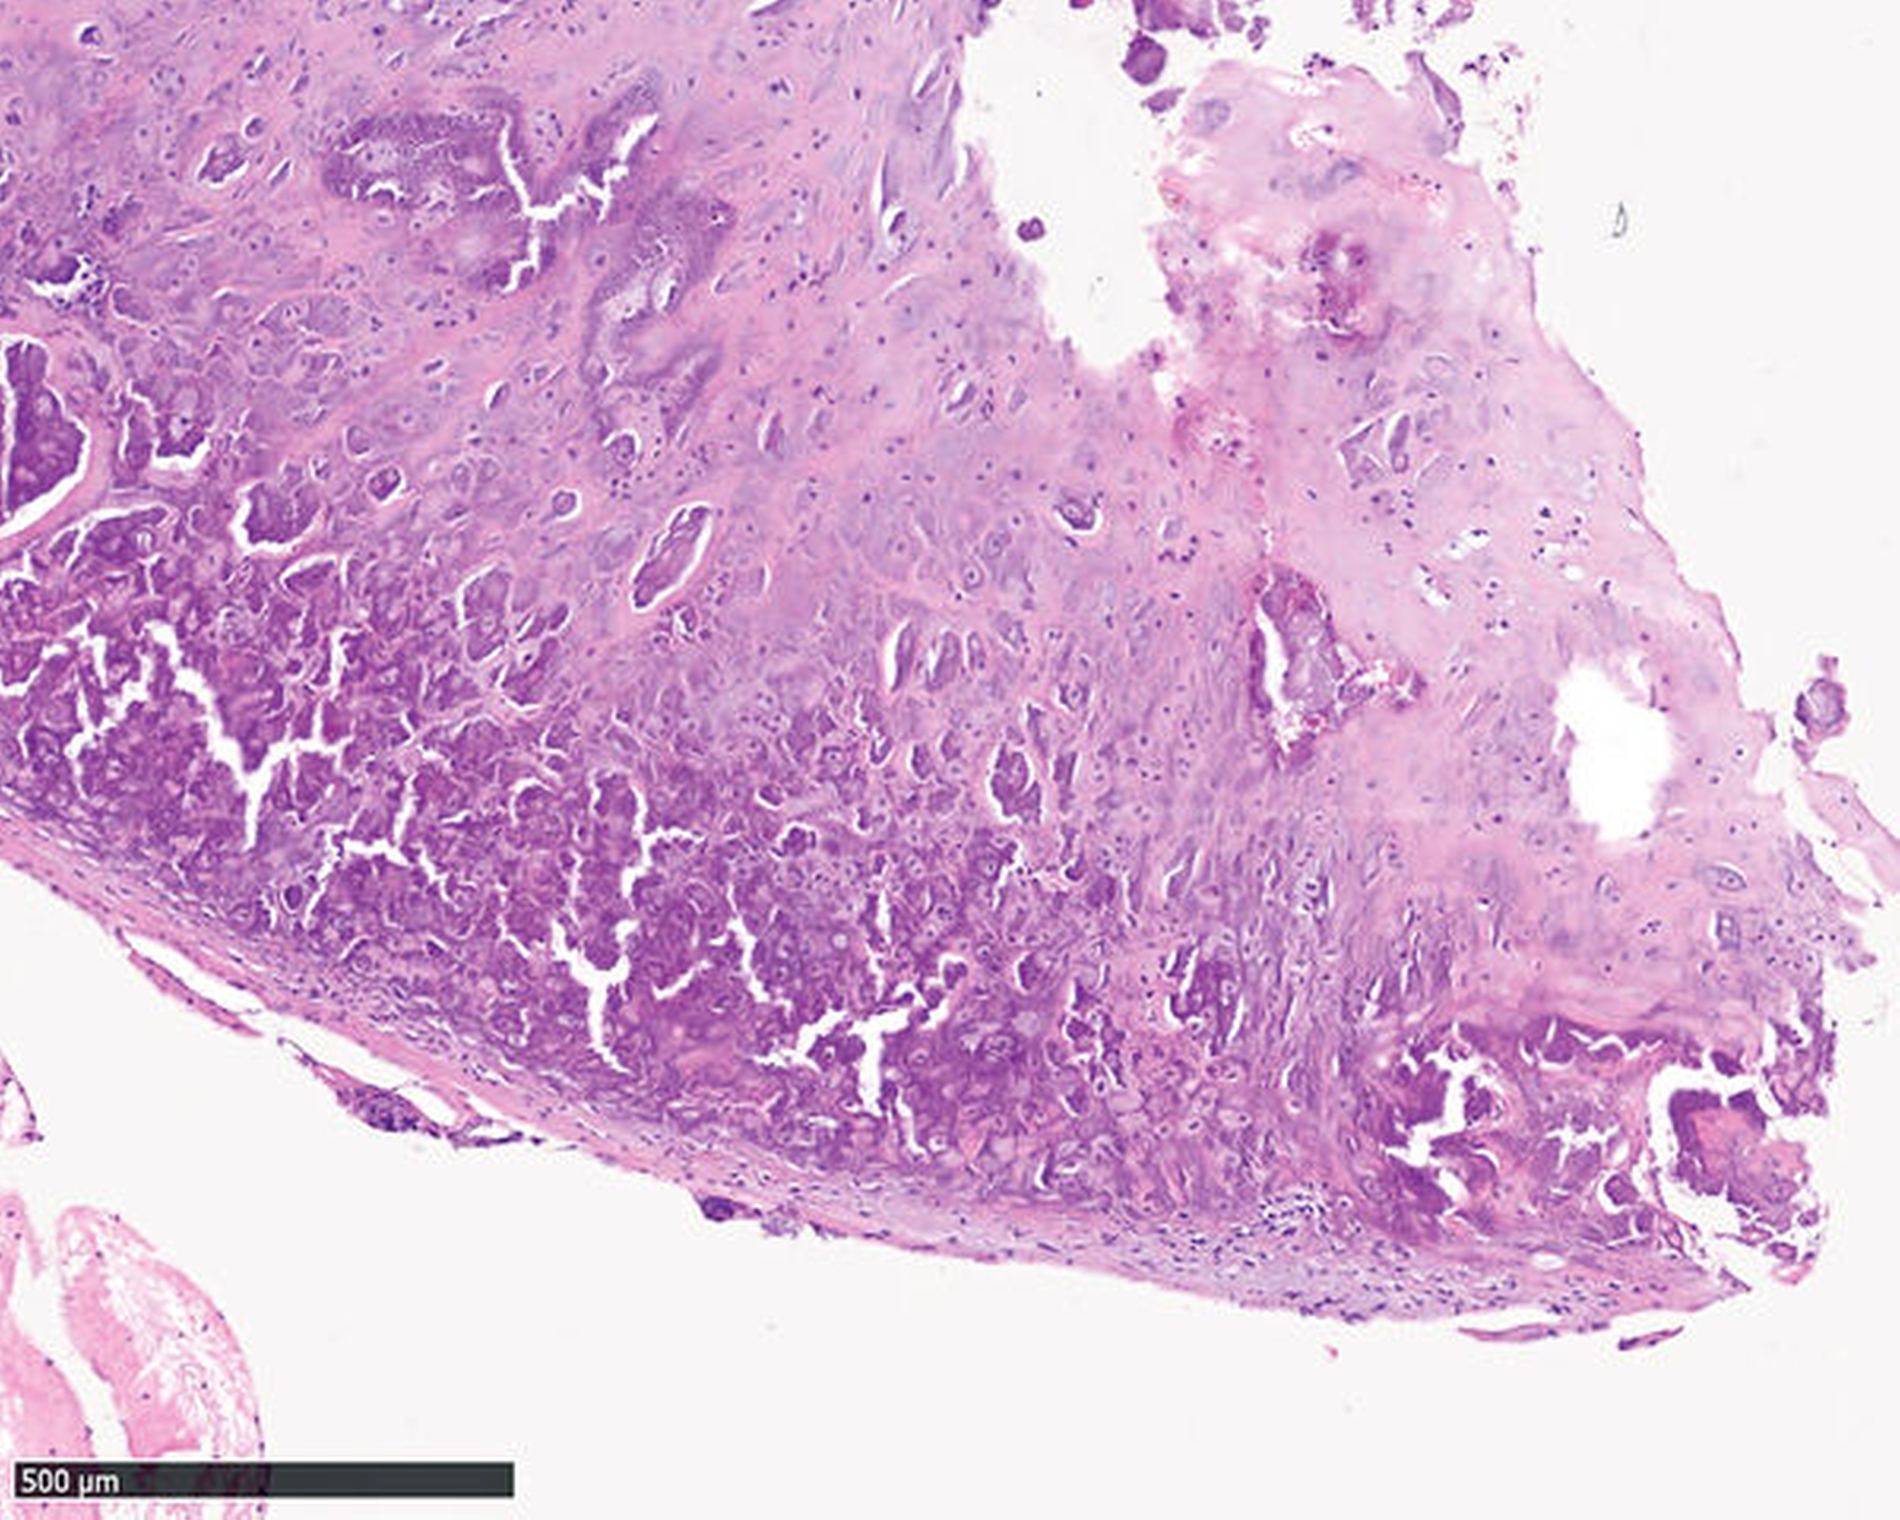

In der navigationsgestützten Probenentnahme in der darauffolgenden Woche präsentierten sich der perikapituläre Kapselapparat als solide kalzifiziert und verdickt sowie der Inhalt des Zystenkavums und die das Kiefergelenk umgebende Raumforderung – die soweit möglich entfernt wurde – als gallertartige Masse mit kleinen, kristallartigen Kalzifikationen (Abbildung 3). Die histopathologische Befundung zeigte die Charakteristika einer Kristallarthropathie mit assoziierter Fremdkörper- und Entzündungsreaktion, passend zu einer Kalziumpyrophosphat- Arthropathie (Abbildung 4). Nach unauffälligem postoperativem Verlauf konnte die Patientin entlassen werden. Im Rahmen der klinischen Untersuchung nach zwei Wochen unter Therapie mit einem nichtsteroidalen Antirheumatikum (NSAR) war sie bei vollständig regredienter Schwellung beschwerdefrei.

Da eine abschließende Bewertung der CPDD auf Basis radiologischer Daten nicht möglich ist, sollte die Diagnosestellung mittels histopathologischer Befundsicherung erfolgen. Wegweisend für die CPDD ist dabei der histologische Nachweis von Kalziumpyrophosphat-Kristallen. Aufgrund der unterschiedlich progredienten Verlaufsformen bedarf es verschiedener therapeutischer Ansätze. Zur Symptomkontrolle wird daher bei moderater Ausprägung die Gabe nichtsteroidaler Antirheumatika (NSAR), Colchicin sowie die intraartikuläre oder systemische Glukokortikoidgabe empfohlen [Koitschev et al., 2003; Announ und Guerne, 2007; Andrés et al., 2018]. Hingegen sollte bei fortgeschrittener Knochen- und Weichteilbeteiligung die chirurgische Entfernung der kalzifiziert-kristallinen Masse sowie des destruierten Knochen- und Weichgewebes zur Linderung der Beschwerden und Wiederherstellung der Funktion erfolgen [Meng et al., 2011; Kwon et al., 2018].